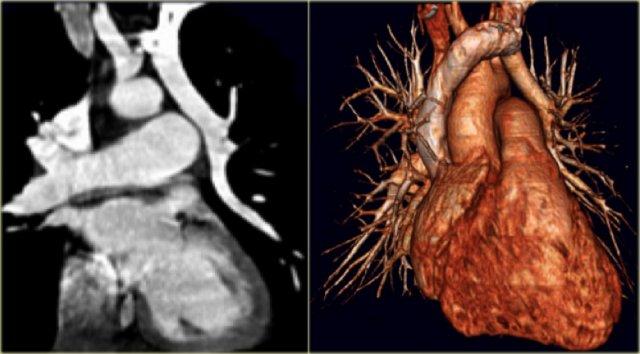

On the left the reconstructions demonstrating a double aortic arch.

There are branches coming off the right arch and branches coming off the left arch.

The right arch is typically larger and higher than the left.

There is a complete ring that encircles the esophagus and the trachea and usually there is stridor or dysphagia.

Two brachiocephalic arteries arise on each side separately (four vessel sign).

The findings are:

- four vessel sign

- double arch

- right arch higher and larger

- esophagus and trachea are completely encircled

The narrowing of the trachea is seen on the axial images, but better appreciated on the MPR and Volume Rendered image.